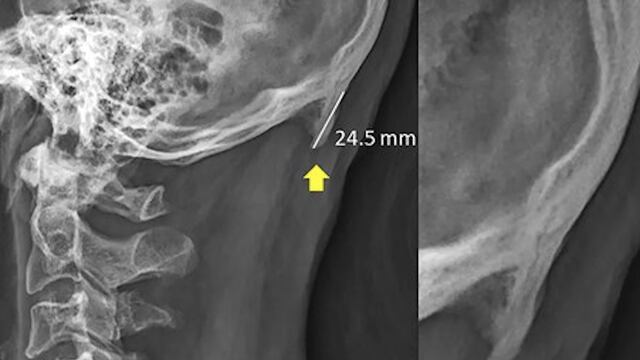

Tras analizar cientos de radiografías, los científicos encontraron que en la base del cráneo de 400 adultos de entre 18 y 86 años estaba creciendo una especie de cuerno que por su posición y los movimientos de la cabeza, se adjudicó a la postura que se adopta generalmente para ver el celular; además, se dieron cuenta que entre más joven era la persona, más grande era la protuberancia.

Según explicó e estudio publicado en Scientific Reports, esta formación es un espolón desarrollado cuando la inflamación daña al cartílago en las articulaciones, lo que se genera por movimientos repetitivos y poco usuales; sobre él los investigadores detallaron que se trata de una "exostosis prominente ... que emana de la proturbancia occipital externa”.

De acuerdo con la investigación, los espolones identificados midieron entre 10 y 31 milímetros, pero los más grandes incluso podían sentirse a través de la piel en la parte trasera de la cabeza, en donde se estaría formando por la continua “flexión de la cabeza hacia adelante”, aunado a una mala postura.

Foto: Scientific Reports / David Shahar y Mark Sayers